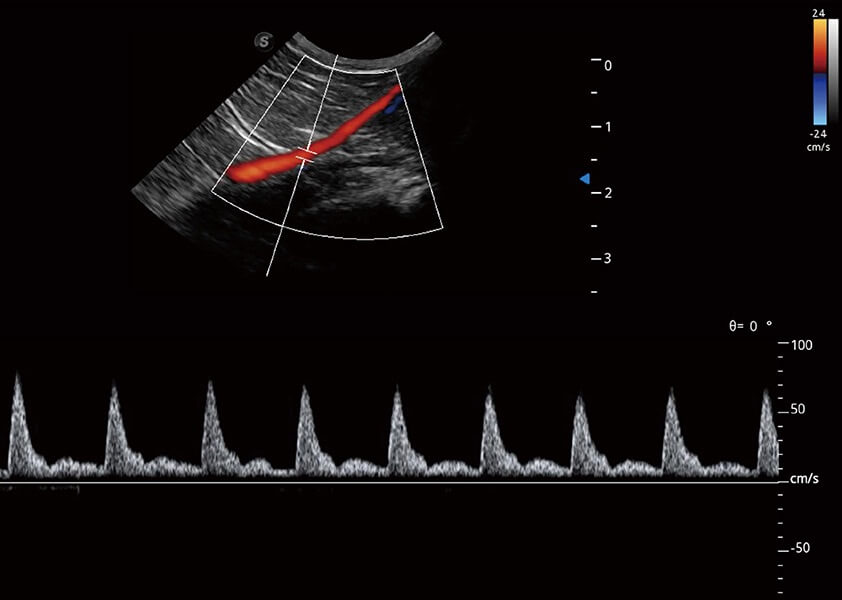

(猫)髂动脉血流频谱

(犬)胆囊泥沙